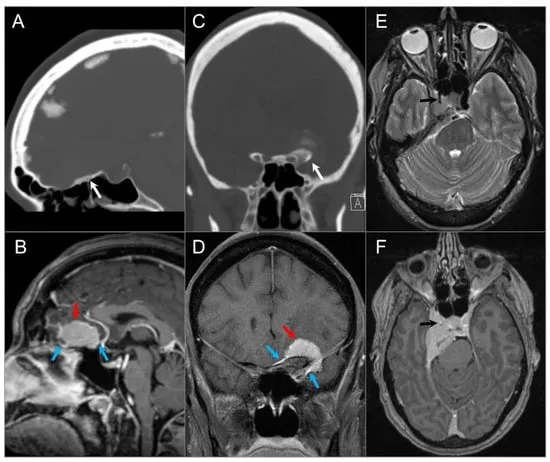

- Chordoma: Midline (clivus), destructive, T2 hyperintense, avid enhancement.

- Chondrosarcoma: Off-midline (petroclival), T2 hyperintense, "rings & arcs" calcification (CT better for Ca++).

- CT Scan: Details bony erosion, calcifications.